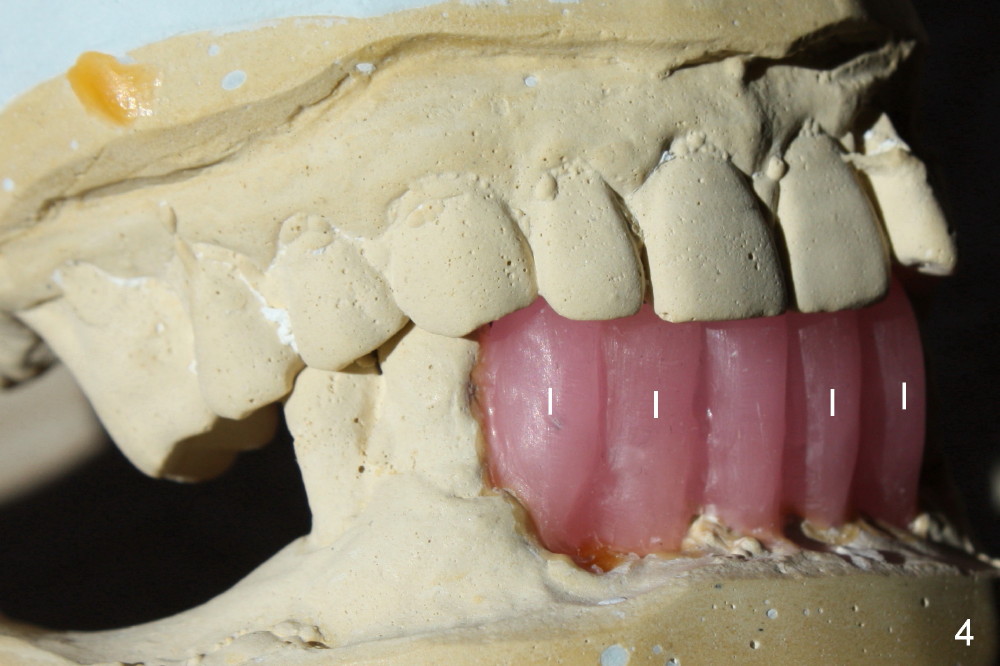

A 52-year-old man seeks treatment 2 months following loss of #22-27 fixed partial denture (FPD) (Fig.1,2).  The remaining dentition has moderate to severe chronic periodontitis.  Scaling & root planing has been done for the upper arch.  Full mouth reconstruction is planned for the lower one in two steps.  In the first procedure, the teeth #18, 20 and 21 are extracted; an incision is made from #20 to #27; two immediate implants are placed at the sites of #20,21 (one or two piece, Fig.3,5 X); another two implants at #22,27 (recently healed sites: Fig.3-5: I) and two one piece implants at lateral incisor region (I: for an implant supported FPD).  In case one of the lower left premolars cannot have an implant due to proximity to the nerve, a FPD can be fabricated in the canine/premolar sextant. A splinted immediate provisional restoration will be fabricated from #20-27 immediately.